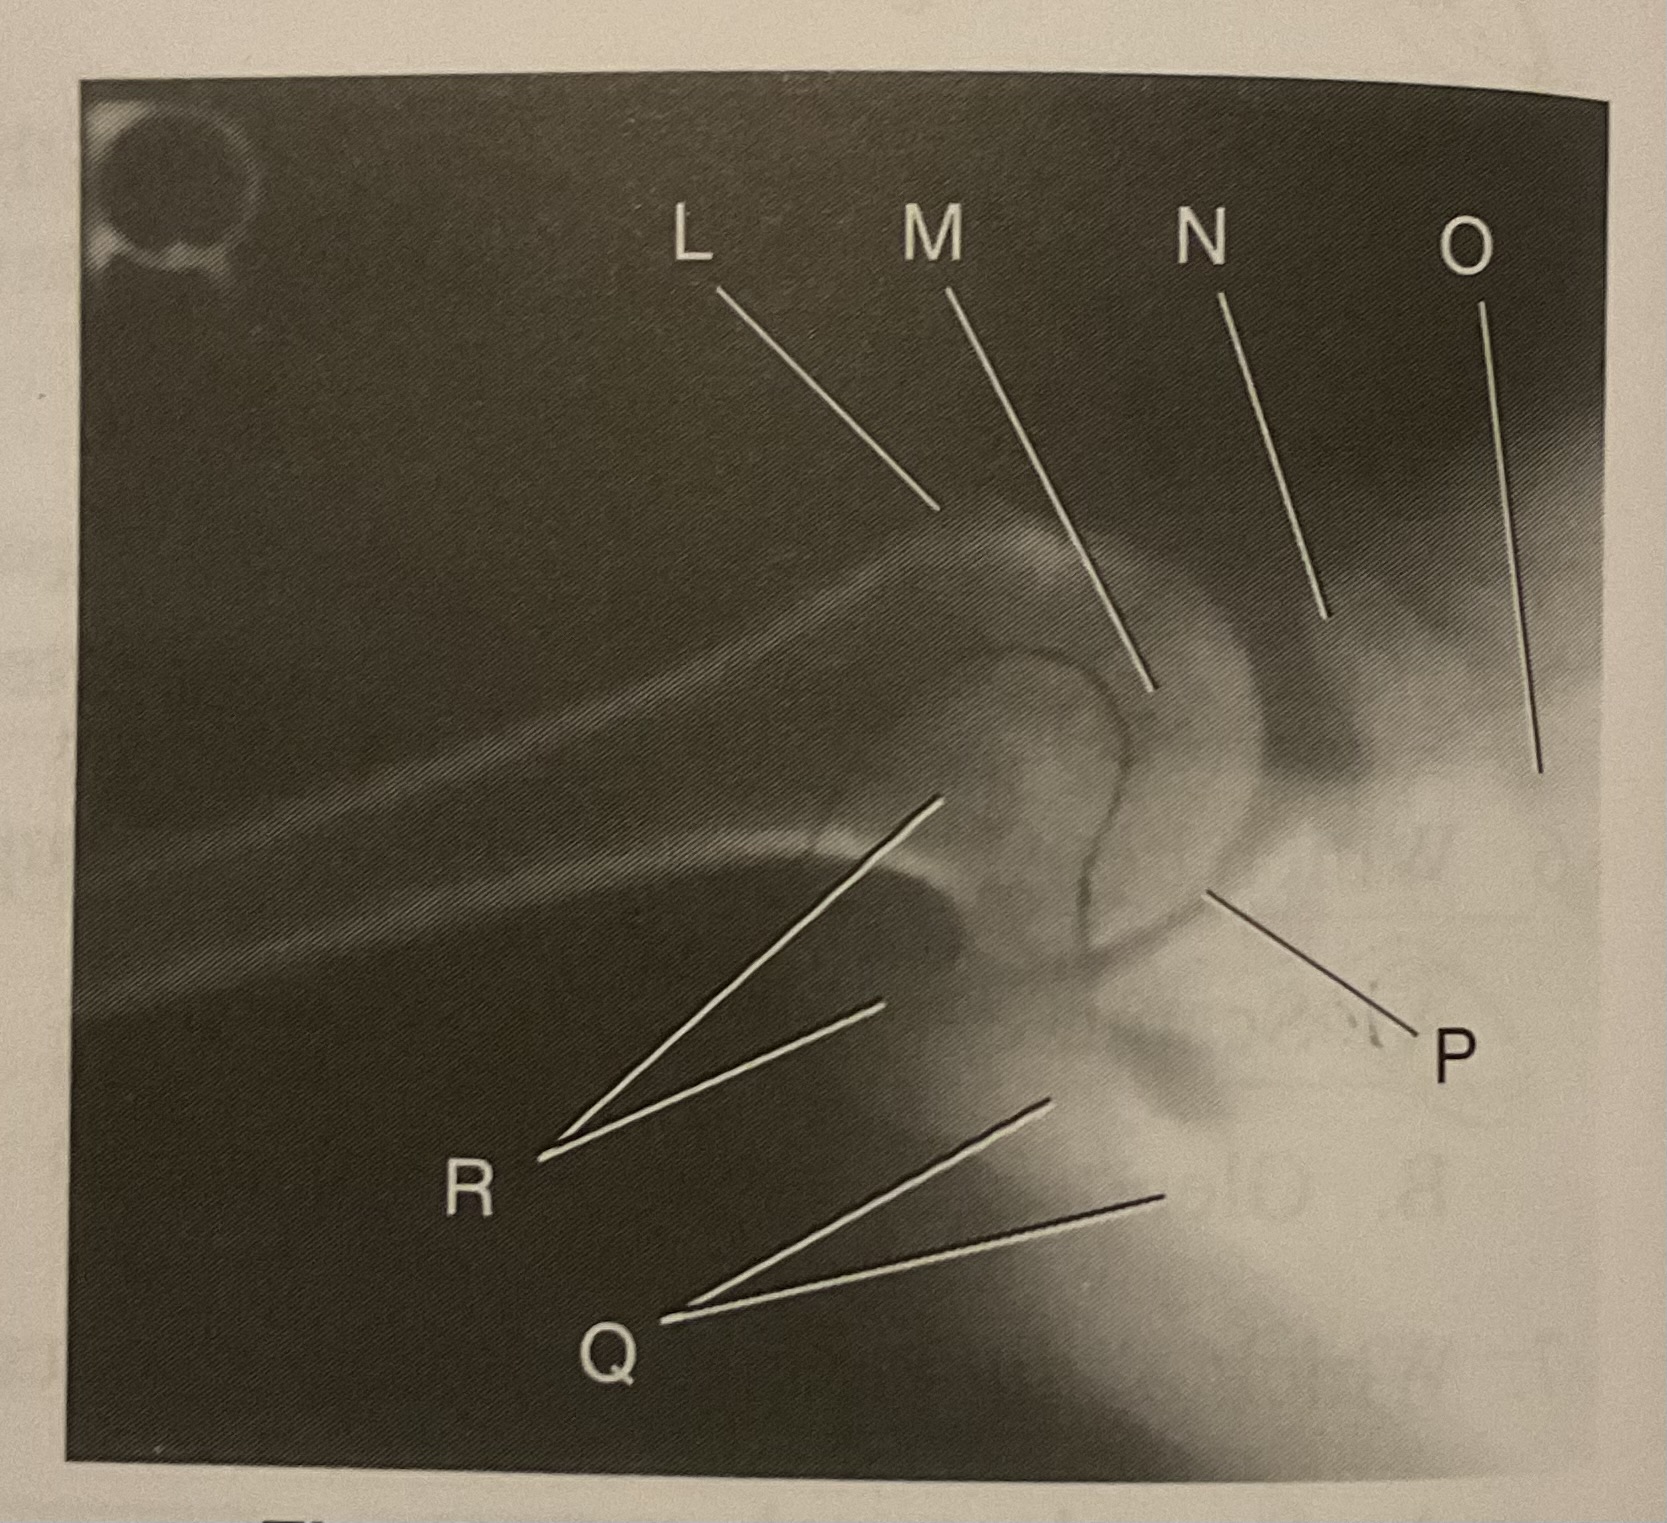

What AP projection does this image represent?

External

L?

Lesser tubercle

M?

Head of humerus

N?

Coracoid process

O?

Clavicle or lateral extremity of clavicle

P?

Glenoid cavity or Scapulohumeral joint

Q?

Spine of scapula

R?

Acromion of scapula

What is the correct term and method for the projection seen in this image?

Inferosuperior axial projection